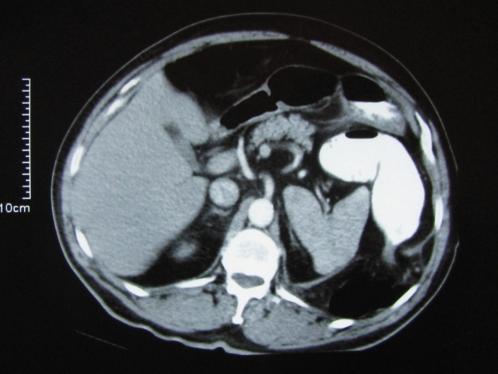

Laparoscopic repair of an incarcerated bochdalek hernia in an elderly man.

Clinics (Sao Paulo). 2012;67(2):199-201. doi: 10.6061/clinics/2012(02)20.